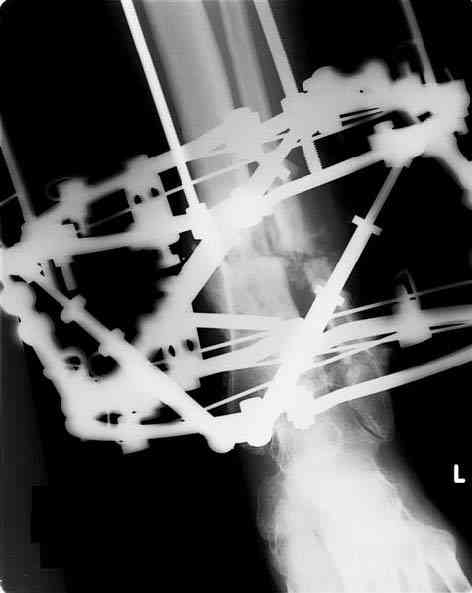

Male 54 years old, diabetic, blind in both eyes, with infected (MRSA) non union distal tibia after fracture 8 month ago. In acute phase treated by ORIF with LCP tibia and fibula. Treatment complicated by infection and after 6 month hardware was removed and treatment continued by cast fixation. You can see malposition of fragments In this stage beginning treated by Ilizarov fixation with use Hexapod system, allows anatomical position of fragments and you see signs of union.

Sorry, I wiil tray now pictures of my case.